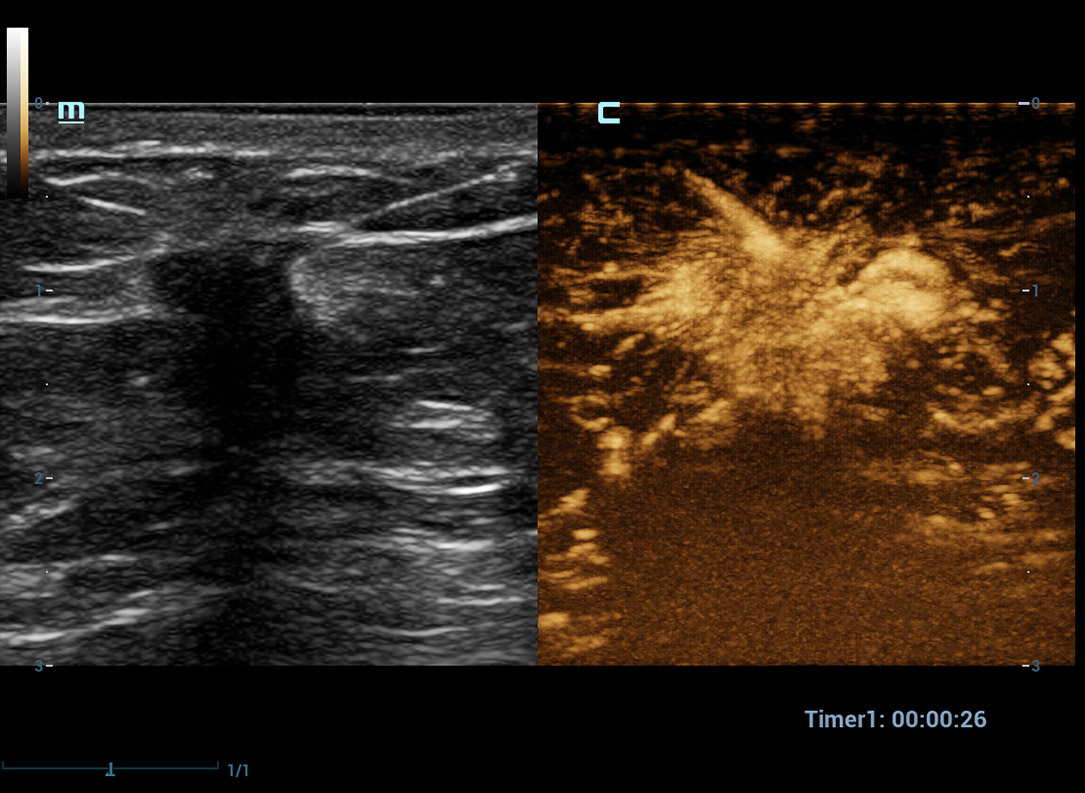

Geavanceerde CEUS

UWN+(Ultra-Wideband Niet-linear) CEUS

CEUS Borst kwaadaardig

Door gebruik te maken van zowel de 2e harmonische als niet-lineaire fundamentele signalen, maaktUWN+ een hoge gevoeligheid van bubbelsignalen en langere contrastperfusie met een lagere MI mogelijk, wat helpt bij tumorbeoordelingen.

UWN+-contrastbeeldvorming

Detecteer en gebruik zowel 2e harmonische als niet-lineaire fundamentele signalen voor het genereren van beelden met:

- Uitstekende agentgevoeligheid, zelfs bij een laag signaal

- Langere perfusietijd met lagere MI

- Betere visualisatie van perfusie van kleine bloedvaten met MFE (Micro Flow Enhancement)